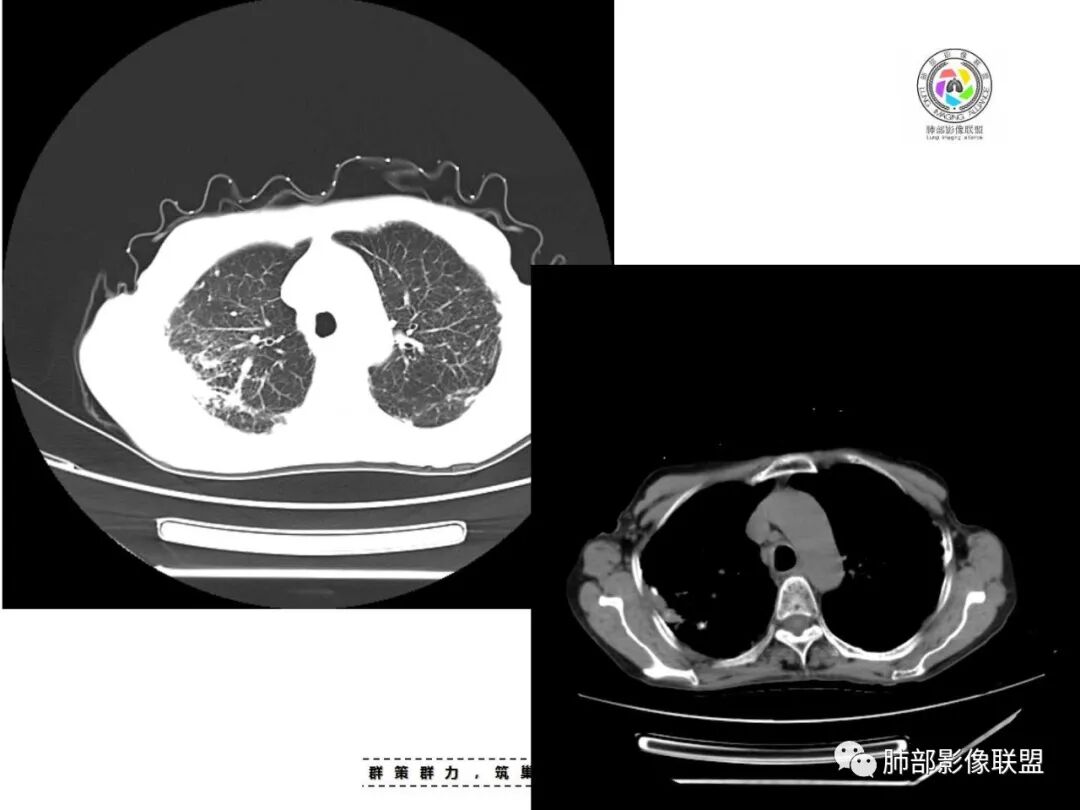

双肺多发斑片,索条及结节影,内可见钙化,右肺上叶后段支气管截断,断端圆钝略扩张,双肺门及纵膈淋巴结钙化,双侧胸膜增厚伴钙化。首先考虑结核。右肺上叶亚段气管分叉处结节,警惕肿瘤

老年女性,双肺索条纤维影,右肺上叶散在卫星灶,树芽征,小叶中心融合,右肺后段支气管圆形截断,实变病灶内支气管扩张,考虑结核。

双肺多发斑片,索条及结节影,内可见钙化,右肺上叶结节影,空泡,右肺上叶后段支气管截断,断端圆钝略扩张,双肺门及纵隔淋巴结钙化,双侧胸膜增厚伴钙化。首先结核肯定会有,右肺上叶结节,考虑腺癌

两肺上叶多发索片小结节影,部分密度较高,中央间质和周围间质都增厚,肺门纵隔淋巴结肿大钙化,基础疾病考虑有尘肺或陈旧结核,需结合相关病史;右肺上叶见斑片点片状模糊影,部分树芽征上叶后段局部细支气管闭塞,考虑感染,结核可能性大,右肺上叶后段病灶实变成团块状,密度低于胸壁肌肉,首先还是考虑结核肉芽肿,治疗后复查除外合并肿瘤可能。

老年女性,67岁,咳嗽、咳痰半月余。双肺可闻及痰鸣音。

胸部CT:双肺上叶多发小结节,沿胸膜下、支气管血管束分布。右上肺斑片实变影、索条影及小叶间隔不均匀增厚,支气管枯枝征?纵隔淋巴结多发肿大,部分有钙化。综合考虑:结节病?尘肺?鉴别:腺癌并癌淋。

就这里不让人放心,是占位吗?支气管是截断的,没有凹陷或者突出阻断,阻断前稍扩张

患者老年女性,亚急性起病,主要症状表现为咳嗽、咳痰半月余,查体:双现呼吸音粗,双肺可闻及痰鸣音。胸部CT:双上肺胸膜下可见多发小叶实变影,双上肺可见多发小叶中心性结节及小叶间隔增厚,右上肺后段可见亚段性实变影,内见多发空洞,前段可见GGO及树芽征,后段局部支气管闭塞,肺门淋巴结肿大并钙化。病灶整体:有气道、间质播散,一元论考虑肺结核合并支气管结核可能性大,建议好好查痰;这样病灶:明显实变+空洞+气道播散,若是结核,痰涂片找到抗酸杆菌应该没问题。建议支气管镜检查助诊,了解有无支气管结核及合并腺癌的可能。

1.双肺片状影、大小不等斑片影、结节影、树芽等,病灶密度偏高多钙化。

2.病灶上肺为主,胸膜下分布为主。双肺病灶明显不对称,右肺块状影较大。

3.纤维条索影广泛杂乱、牵拉,横向分布为主,这点给人也印象很深!

4.纵隔轻度右移。双肺门纵隔淋巴结增大钙化。